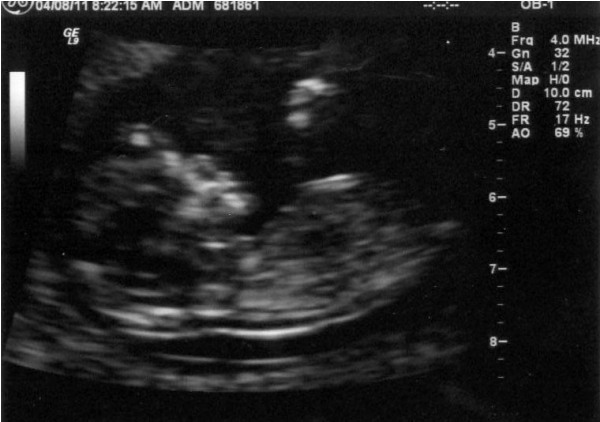

We did the first trimester screening today, which included an in-depth ultrasound. Fox hadn't yet seen the high quality images that we get at the Perinatal Center as compared to the OBGYN's office, so he was in awe at all that we could see.

This is how the baby was positioned at the start of the ultrasound: upside down and very contentto be so. Kind of cute, yes? It kept trying to get back into this position during the whole process.

After some poking, prodding and otherwise trying to convince the kid to get into the position the technician needed, it did eventually cooperate, for a little while. When it tried to change positions, the technician would poke and prod some more. We laughed when we saw a little tongue sticking out. A sign of things to come perhaps?

As indicated, these are the kid's feet. We got a decently good look at the feet and legs, as well as the arms, hands and brain. The arms were crossed, like an Egyptian mummy. During the whole ultrasound, the kid was practicing swallowing, which looked like a bad case of the hiccups.